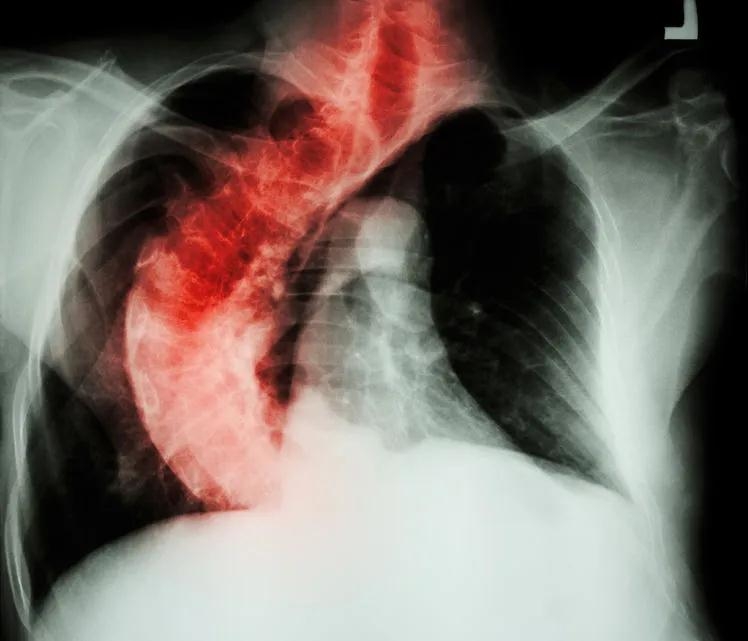

临床观察中发现,多数脊柱侧凸患者因胸廓畸形受限而存在不同程度的呼吸功能受限,表现在走路、上下楼梯等日常轻微活动中即会出现气短气促。

脊柱侧凸常引起胸廓的畸形与运动异常:

(1)胸廓畸形使胸腔容积缩小,使肺实质受压,肺容积缩小,影响肺充气;

(2)气道受压弯曲,使肺通气受阻,肺活量与呼吸流速下降;

(3)双侧胸廓运动不对称,使肺下界移动度减低,前后径扩张受限;

(4)影响呼吸系统发育:若在婴幼儿时期开始出现脊柱侧凸与胸廓畸形,则会导致肺脏发育异常,肺泡增殖减少,在儿童或青少年时期开始出现侧凸的患者,肺泡的大小和功能也会受到影响。同时,肺血管数量随着肺部发育不良也减少。

综合以上原因,脊柱侧凸患者会并发呼吸功能损害。

青少年及较年轻的患者多数是由脊柱侧凸导致胸廓畸形,进而造成限制性通气功能障碍。

成人脊柱侧凸由于肺脏受压,肺泡舒张长期受限,造成肺血气体交换异常,常表现为限制性通气功能障碍与弥散功能障碍混合的肺功能损害。

(1)Cobb角大于90度时,胸腔严重挤压,很容易引发心肺功能衰竭;

(2)Cobb角在50至60度时可检测到肺功能异常;

(3)肺功能异常主要为限制性类型;

(4)肺功能损害的程度与脊柱侧凸的持续时间以及侧凸程度有关。